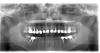

Doc Опубликовано 28 июля, 2011 Поделиться Опубликовано 28 июля, 2011 Отказались от разборных в пользу не разборных. золото рулит, чаще к сожелению приходится ставить не драг. сплав., там чаще корни трещат. Но я думаю трещины корня не всегда собственно от наличия или отсутствия вкладки, проблемы раньше возникают на этапе ретрита... Ну так и зря отказались. Лучше было бы отточить мастерство на разборных, чем отказываться от них. Керамика тоже колется, Вы же не отказались от металлокерамики в пользу железа, а стали, наверное, изучать причины сколов, работать с прикусом и т.д. Если у Вас корни трещат от вкладок, значит просто "Вы их не умеете готовить". А если не трещат, а Вы отказались только потому, что кто-то где-то рассказал, что трещать, то не нужно опираться на слухи. Вот, как раз еще одна пациентка из того же далекого 2000 года. А вот эта же самая пациентка сегодня: Даже несмотря на то же самое "хреновое эндо", которое тот же самый врач делал, что и предыдущие случаи, живет и здравствует. Ни один зуб не требует вмешательства. Ссылка на комментарий